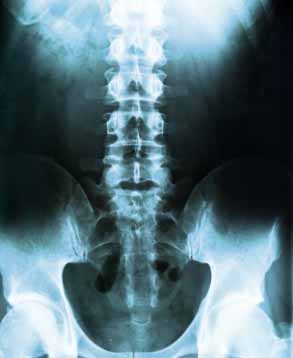

Sacroiliac Joint, Back Problems

Studies have found that 20 to 25% of all chronic lower back pain comes not from the spine but from the sacroliac, or SI Joint, which bears and transfers weight and movement from your upper body to your legs. When the ligaments wear out and the SI joint becomes unstable, it can generate a similar kind of sharp back pain -- or sciatica-like pain down your leg -- as a ruptured disc.

The spine is a complex interconnecting network of nerves, joints, muscles, tendons and ligaments, and all are capable of producing pain. Large nerves that originate in the spine and go to the legs and arms can make pain radiate to the extremities.

Back injuries result from damage, wear, or trauma to the bones, muscles, or other tissues of the back. Common back injuries include sprains and strains, herniated disks, and fractured vertebrae. The lumbar is often the site of back pain. The area is susceptible because of its flexibility and the amount of body weight it regularly bears. It is estimated that low-back pain may affect as much as 50 to 70 percent of the general population in the United States.